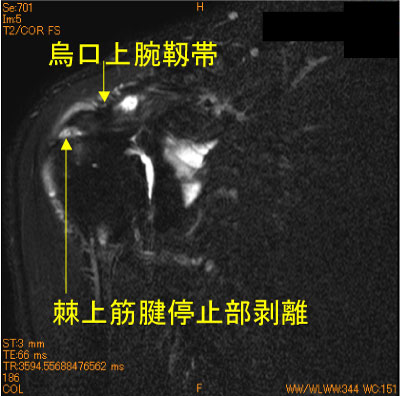

50代男性。スキーで転倒後9日後MRI。スキー歴40年。

棘上筋腱停止部の大結節superior facetからの剥離を認める。

![]() Obl. Cor T2WI 脂肪抑制 |